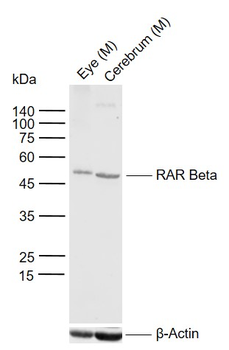

RARB Rabbit Polyclonal Antibody [orb11327]

FC, ICC, IF, IHC-Fr, IHC-P, WB

Bovine, Canine, Gallus, Porcine, Rat

Human, Mouse

Rabbit

Polyclonal

Unconjugated

50 μl, 100 μl, 200 μlTIG2 Rabbit Polyclonal Antibody [orb11481]